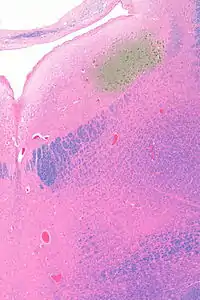

Micrograph showing the locus coeruleus (upper-right of image) in an axial section of the pons. The fourth ventricle (quasi-triangular white area) is in the upper-left of the image. The midline is seen on the left. The large white area in the upper-left corner is where the cerebellum would be. HE-LFB stain.